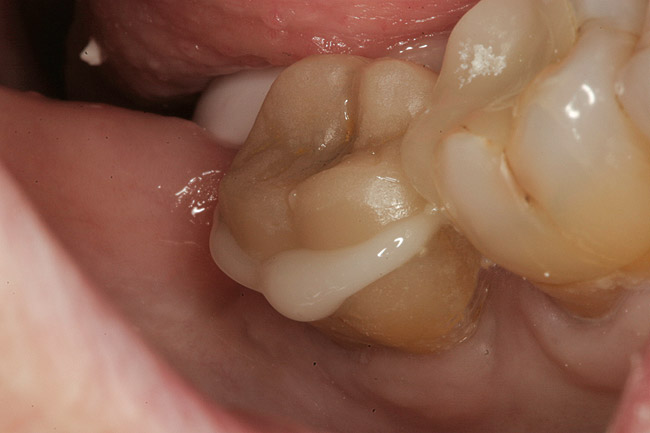

Figure 2  Facial view (Fig 2) and occlusal view (Fig 3) of nonretentive adhesively retained ("table-top") preparation.

Figure 2

A 70-year-old patient presented with symptoms of a cracked tooth scenario, with intermittent pain upon chewing and thermal sensitivity. The diagnosis was supported through various tests, which determined the lower right second molar had an incomplete fracture that extended from the distal marginal ridge to the mesial marginal ridge. After treatment options were presented, an all-ceramic restoration was decided upon. The tooth was prepared for a nonretentive, adhesively retained all-ceramic restoration ("table top" preparation) (Figure 2 and Figure 3). After the preparation was completed a mild self-etching adhesive was applied to the dentin according to the manufacturer's instruction (Figure 4). There was little concern, if any, of the adhesive reaching the band of exposed enamel. The adhesive was light-polymerized for 5 seconds to secure the layer to the dentin (Figure 5). To eliminate the oxygen-inhibited layer a water-soluble gel was applied to the adhesive and further light-polymerization was completed (Figure 6 and Figure 7). For direct digital scanning cases in which a powdering technique is employed for image capture, it may be more difficult to remove the powder after scanning if the oxygen-inhibited layer is still present.